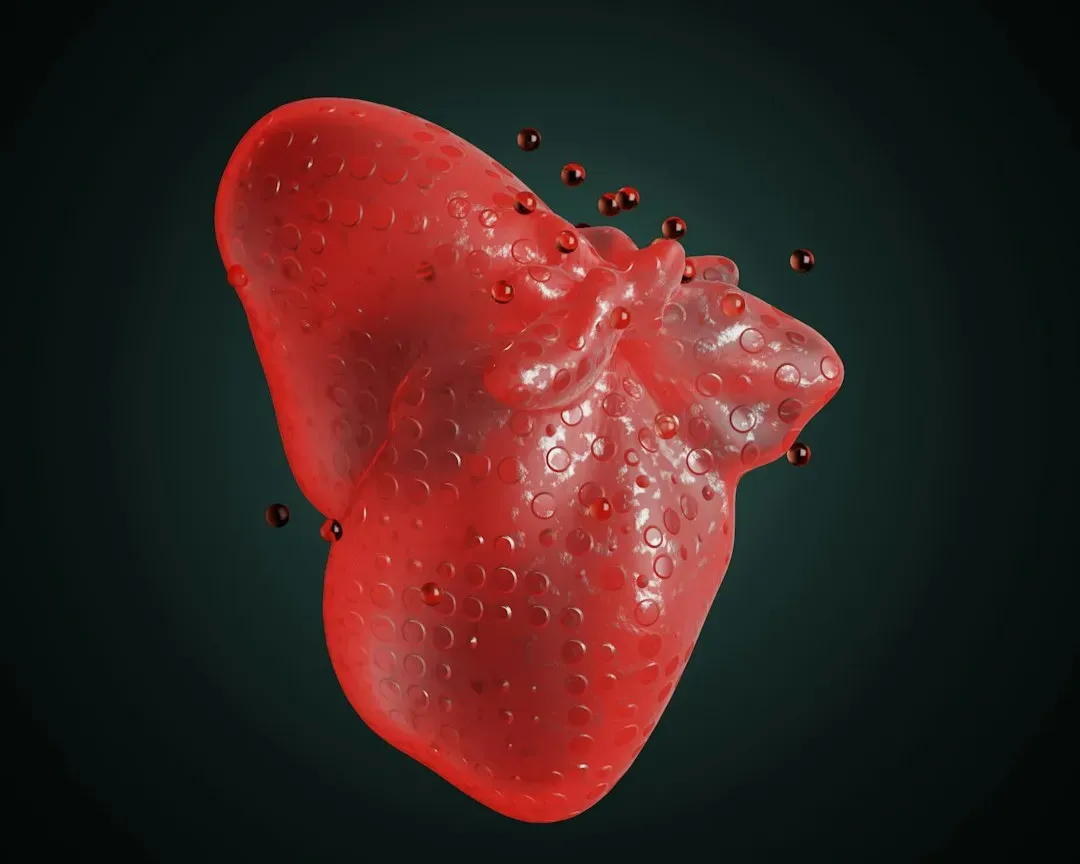

Every day, your immune system is waging countless tiny battles you never feel or see. Bacteria on your skin, viruses in the air, and abnormal cells that pop up from everyday DNA copying errors all get scanned, tagged, and, if needed, destroyed. White blood cells patrol like neighborhood guards, antibodies recognize familiar threats from past infections or vaccines, and inflammation acts as an alarm system calling in reinforcements. When everything works smoothly, you stay healthy and barely notice that anything happened at all.

What’s truly fascinating is that your immune system learns from experience and can refine its response over time. Vaccines essentially train it like a rehearsal before a real performance, so when the actual pathogen appears, your body already knows the moves. On the flip side, when the system gets confused, it can overreact to harmless things like pollen, or even attack your own tissues in autoimmune diseases. That’s where lifestyle choices like sleep, stress management, and diverse nutrition come in, because they support a more balanced immune response. It’s not about “boosting” everything blindly; it’s about helping your internal defense team distinguish friend from foe more accurately.